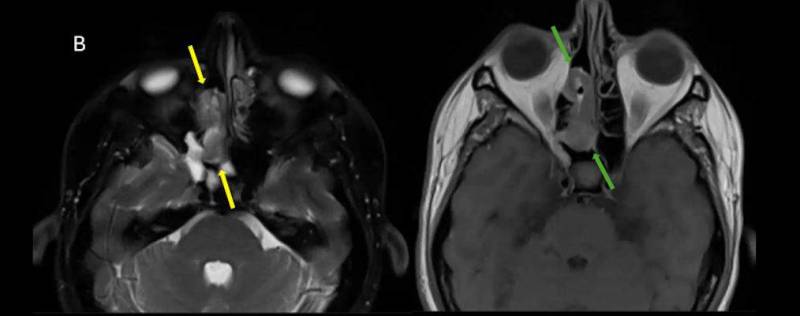

- B) Aksiyel T2A (oklar) ve T1A (oklar) görüntülerde lezyonun süperior nazal kavitede ve ara sinyal intensitede olduğu izleniyor.